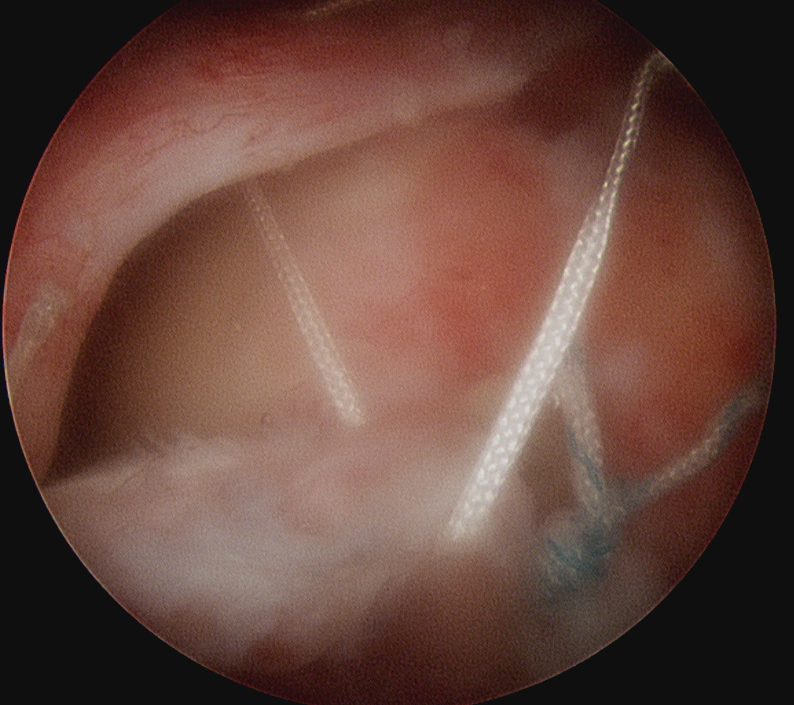

Margin convergence sutures

Release infraspinatus tendon posteriorly and assess mobility

Repair infraspinatus with a combination of margin convergence and posterior suture anchors onto posterior greater tuberosity

True partial repair of the rotator cuff with exposed triangle of greater tuberosity